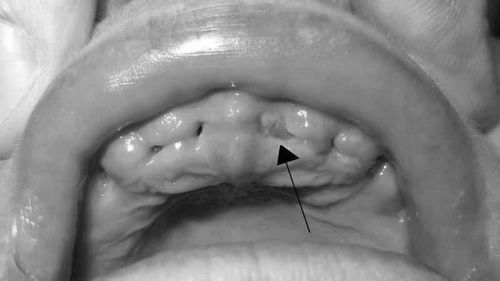

На даній фотографії зображена лунка після видалення зуба в стадії нормально протікає загоєння

Потрібно ретельно дотримуватись рекомендацій лікаря щодо харчування в перші дні після операції. Однак якщо побіліла ясна після видалення зуба, це нормально. Через добу приблизно утворюється спеціальний наліт на яснах, вона може біліть або пожовтіти. Це не гнійні скупчення, а випіт фібрину.Можливе виникнення та інших ускладнень після проведення процедури і видалення зуба. У будь-якому випадку потрібно запам'ятати, що якщо виникло запалення після видалення зуба, лікування проводиться тільки під контролем фахівця.

Нормальний стан лунки після видалення зуба через 3 тижні